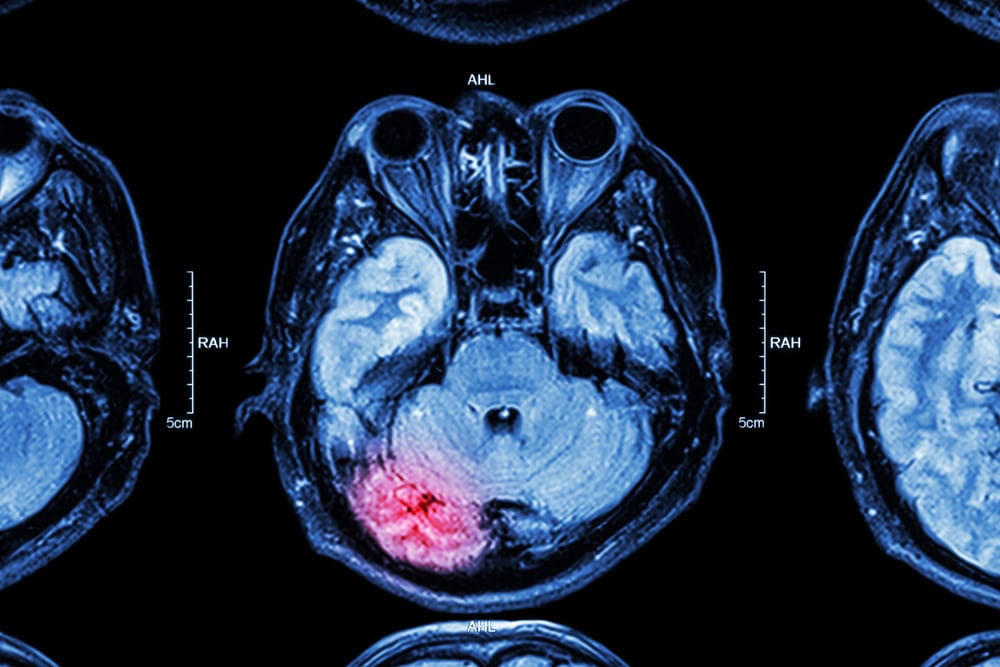

A traumatic brain injury is any type of damage to the brain that occurs from an external force that is great enough to induce bruising, bleeding, inflammation, or swelling, not READ MORE

A traumatic brain injury (TBI) can result from a severe auto accident. In terms of devastation, it is one of the worst injuries a person can suffer. Aside from the READ MORE